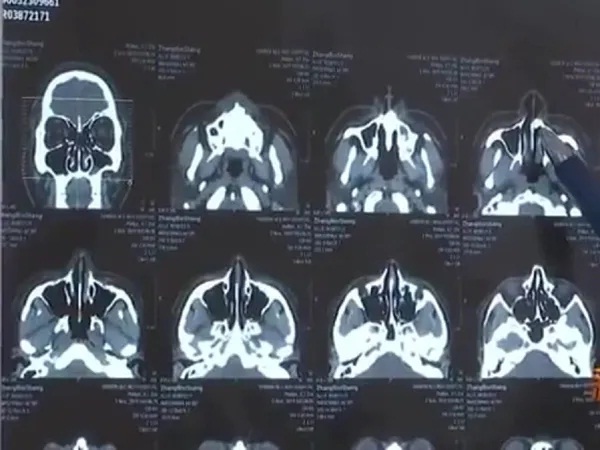

ਚੀਨ ਦੇ ਝਾਂਗ ਬਿੰਸੇਂਗ (Zhang Binsheng) ਨੂੰ 3 ਮਹੀਨੇ ਤੋਂ ਆਪਣੇ ਨੱਕ ਜ਼ਰੀਏ ਸਾਹ ਲੈਣ ਵਿਚ ਸਮੱਸਿਆ ਹੋ ਰਹੀ ਸੀ। ਫਿਰ ਉਸ ਨੇ ਡਾਕਟਰਾਂ ਨੂੰ ਦਿਖਾਉਣ ਦਾ ਫੈਸਲਾ ਲਿਆ। ਝਾਂਗ ਨੇ ਡਾਕਟਰਾਂ ਨੂੰ ਦੱਸਿਆ ਕਿ ਉਹ ਰਾਤ ਵੇਲੇ ਸੌਂ ਨਹੀਂ ਪਾਉਂਦਾ ਅਤੇ ਉਸ ਨੂੰ ਸਾਹ ਲੈਣ ਵਿਚ ਮੁਸ਼ਕਲ ਹੁੰਦੀ ਹੈ। ਉਨ੍ਹਾਂ ਨੇ ਆਪਣੀ ਨੱਕ ਵਿਚੋਂ ਲਗਾਤਾਰ ਗੰਧ ਆਉਣ ਦੀ ਵੀ ਸ਼ਿਕਾਇਤ ਕੀਤੀ। ਡਾਕਟਰਾਂ ਨੇ ਉਸ ਨੂੰ ਐਕਸ ਰੇਅ ਕਰਾਉਣ ਦੀ ਸਲਾਹ ਦਿੱਤੀ।

ਜਦੋਂ ਐਕਸ ਰੇਅ ਦੀ ਰਿਪੋਰਟ ਆਈ ਤਾਂ ਝਾਂਗ ਆਪਣੀ ਨੱਕ ਦੀ ਨਲੀ ਦੇ ਪਿੱਛੇ ਉੱਚ ਘਣਤਾ ਵਾਲਾ ਪਰਛਾਵਾਂ ਦੇਖ ਕੇ ਹੈਰਾਨ ਰਹਿ ਗਿਆ। ਡਾਕਟਰਾਂ ਦਾ ਮੰਨਣਾ ਸੀ ਕਿ ਇਹ ਪਰਛਾਵਾਂ ਝਾਂਗ ਦੀ ਨੱਕ ਵਿਚ ਉੱਗ ਆਏ ਦੰਦ ਦਾ ਸੀ, ਜੋ ਇਕ ਹਾਦਸੇ ਦੇ ਕਾਰਨ ਉਸ ਦੀ ਨੱਕ ਵਿਚ ਉੱਗ ਆਇਆ ਸੀ। ਰਿਪੋਰਟ ਮੁਤਾਬਕ ਜਦੋਂ ਝਾਂਗ 10 ਸਾਲ ਦਾ ਸੀ ਉਦੋਂ ਉਹ ਇਕ ਮਾਲ ਦੀ ਤੀਜੀ ਮੰਜ਼ਿਲ ਤੋਂ ਹੇਠਾਂ ਡਿੱਗ ਪਿਆ ਸੀ। ਉਸ ਦੇ ਦੋ ਦੰਦ ਟੁੱਟੇ ਸਨ ਪਰ ਹਾਦਸੇ ਦੇ ਬਾਅਦ ਸਿਰਫ ਇਕ ਟੁੱਟੇ ਹੋਏ ਦੰਦ ਨੂੰ ਲੱਭਿਆ ਜਾ ਸਕਿਆ ਸੀ।

ਡਾਕਟਰਾਂ ਦੇ ਮੁਤਾਬਕ ਅਜਿਹਾ ਲੱਗਦਾ ਹੈ ਕਿ ਦੂਜਾ ਦੰਦ ਕਿਸੇ ਤਰ੍ਹਾਂ ਜੜ ਤੋਂ ਉਖੜ ਗਿਆ ਅਤੇ ਉਸ ਦੇ ਨੱਕ ਦੇ ਅੰਦਰ ਉੱਗ ਗਿਆ। ਇਸ ਗੱਲ 'ਤੇ ਦੋ ਦਹਾਕਿਆਂ ਤੱਕ ਨਾਂ ਤਾਂ ਝਾਂਗ ਨੇ ਅਤੇ ਨਾ ਹੀ ਉਸ ਦੇ ਪਰਿਵਾਰ ਨੇ ਧਿਆਨ ਦਿੱਤਾ। ਅੱਜ ਝਾਂਗ ਦੀ ਉਮਰ 30 ਸਾਲ ਹੋ ਚੁੱਕੀ ਹੈ ।

ਭਾਵੇਂਕਿ 30 ਮਿੰਟ ਦੀ ਸਰਜਰੀ ਦੇ ਬਾਅਦ ਝਾਂਗ ਦੀ ਨੱਕ ਤੋਂ ਇਕ ਸੈਂਟੀਮੀਟਰ ਲੰਬੇ ਦੰਦ ਨੂੰ ਕੱਢਿਆ ਗਿਆ, ਜਿਸ ਮਗਰੋਂ ਉਸ ਨੇ ਸੁੱਖ ਦਾ ਸਾਹ ਲਿਆ।